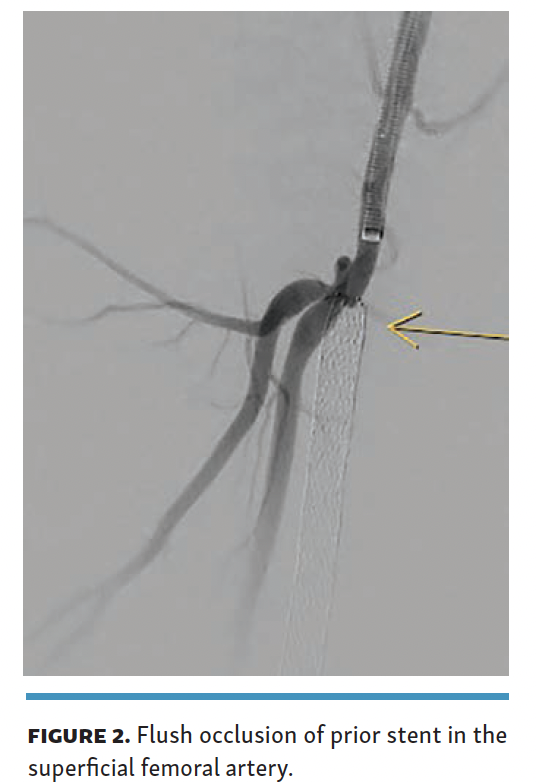

For the procedure, 8F arterial access was obtained from the contralateral side with ipsilateral posterior tibial venous access (6F, 25-cm sheath). Diagnostic angiogram demonstrated a flush occlusion of the prior SFA stent with no proximal landing zone in the SFA (Figure 2).